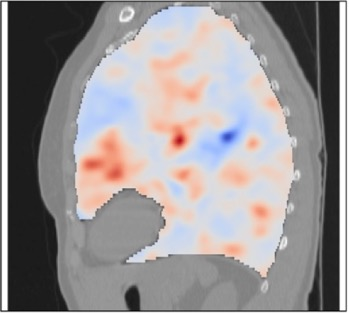

Deformable image registration is a fundamental task in medical image analysis and plays a crucial role in a wide range of clinical applications. Recently, deep learning-based approaches have been widely studied for deformable medical image registration and achieved promising results. However, existing deep learning image registration techniques do not theoretically guarantee topology-preserving transformations. This is a key property to preserve anatomical structures and achieve plausible transformations that can be used in real clinical settings. We propose a novel framework for deformable image registration. Firstly, we introduce a novel regulariser based on conformal-invariant properties in a nonlinear elasticity setting. Our regulariser enforces the deformation field to be smooth, invertible and orientation-preserving. More importantly, we strictly guarantee topology preservation yielding to a clinical meaningful registration. Secondly, we boost the performance of our regulariser through coordinate MLPs, where one can view the to-be-registered images as continuously differentiable entities. We demonstrate, through numerical and visual experiments, that our framework is able to outperform current techniques for image registration.